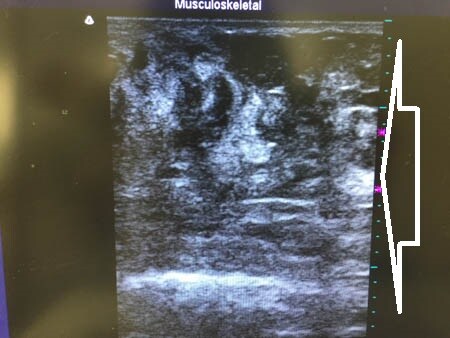

3Dタッチビュー(=超音波)で

皮下脂肪層の変化を見てみましょう。

上腹部。